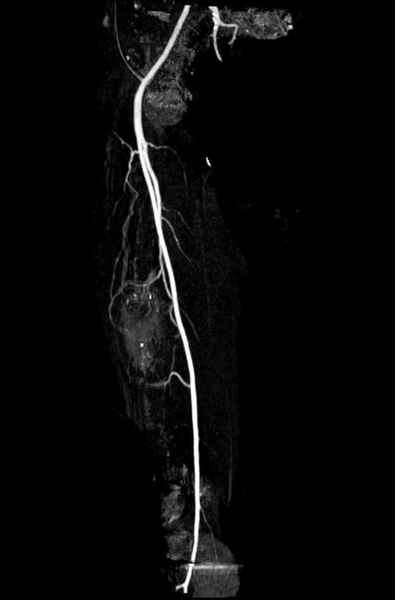

С минимальным рассверливанием и ретроградным методом провели остеосинтез бедра 12 мм гвоздем. (17-20)

Кровопотеря во время операции меньше 100 мл.